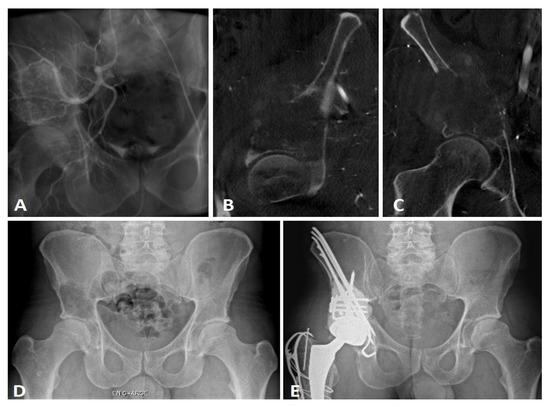

2.2. Extensive Acetabular Bone Loss Management

2.2.1. Treatment Strategy

2.2.2. Surgical Procedure

| Associated treatments | Radiation therapy | Preoperative | 8 (38.1%) |

| Postoperative (n = 18) | 14 (77.8%) | ||

| Preoperative embolization | 3 (14.3%) | ||